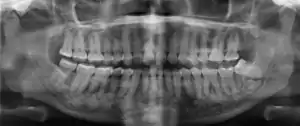

| Florid osseous dysplasia of the mandible | |

| Diagnostic method | X-ray, CBCT scan, vitality testing of teeth |

Diagnosis is important so that the treating doctor does not confuse it for another periapical disease such as rarefying osteitis or condensing osteitis. Incorrect diagnosis could lead to unnecessary root canal treatments. It can be diagnosed by radiographic appearance. Confirming the tooth is vital, as is noting the demographic (African American females).[1][2][3]